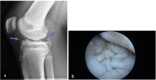

Case presentation: We describe the clinical manifestations, radiological pictures and disease course of other causes of limping in childhood, through a case series of seven cases and a brief discussion of each disease.

Conclusions: although trauma is the most common cause of acute limping, when there is no history of traumatic events and the limping has a chronic course, Juvenile Idiopathic Arthritis is usually the most likely clinical diagnosis. However, other some rare conditions should be taken into account if JIA is not confirmed or if it presents with atypical clinical picture.

Keywords: CACP syndrome; COPA syndrome; Chronic nonbacterial osteomyelitis; Differential diagnosis; JIA; Limping child; Lyme arthritis; Neuroblastoma; Non-traumatic limping; Pigmented villonodular synovitis.